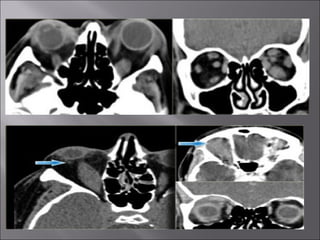

Ultrasound and CT scans provide anatomical images of the orbit, while color Doppler imaging provides visualizations of vascular structures and blood flow within lesions. These imaging techniques are used to evaluate a variety of orbital conditions involving blood vessels, infections, tumors, congenital issues, trauma, and more, and can help identify vascular disorders, thrombosis, treatment responses, and dynamic changes in benign tumors over time.